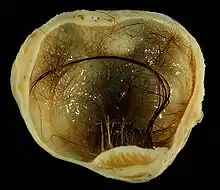

| A small (4 cm) dermoid cyst of an ovary, discovered during Cesarean section | |

A mature teratoma is a grade 0 teratoma. They are highly variable in form and histology, and may be solid, cystic, or a combination of the two. A mature teratoma often contains several different types of tissue such as skin, muscle, and bone. Skin may surround a cyst and grow abundant hair (see dermoid cyst). Mature teratomas generally are benign, with 0.17-2% of mature cystic teratomas becoming malignant.[16]

Dermoid cyst

A dermoid cyst is a mature cystic teratoma containing hair (sometimes very abundant) and other structures characteristic of normal skin and other tissues derived from the ectoderm. The term is most often applied to teratoma on the skull sutures and in the ovaries of females.